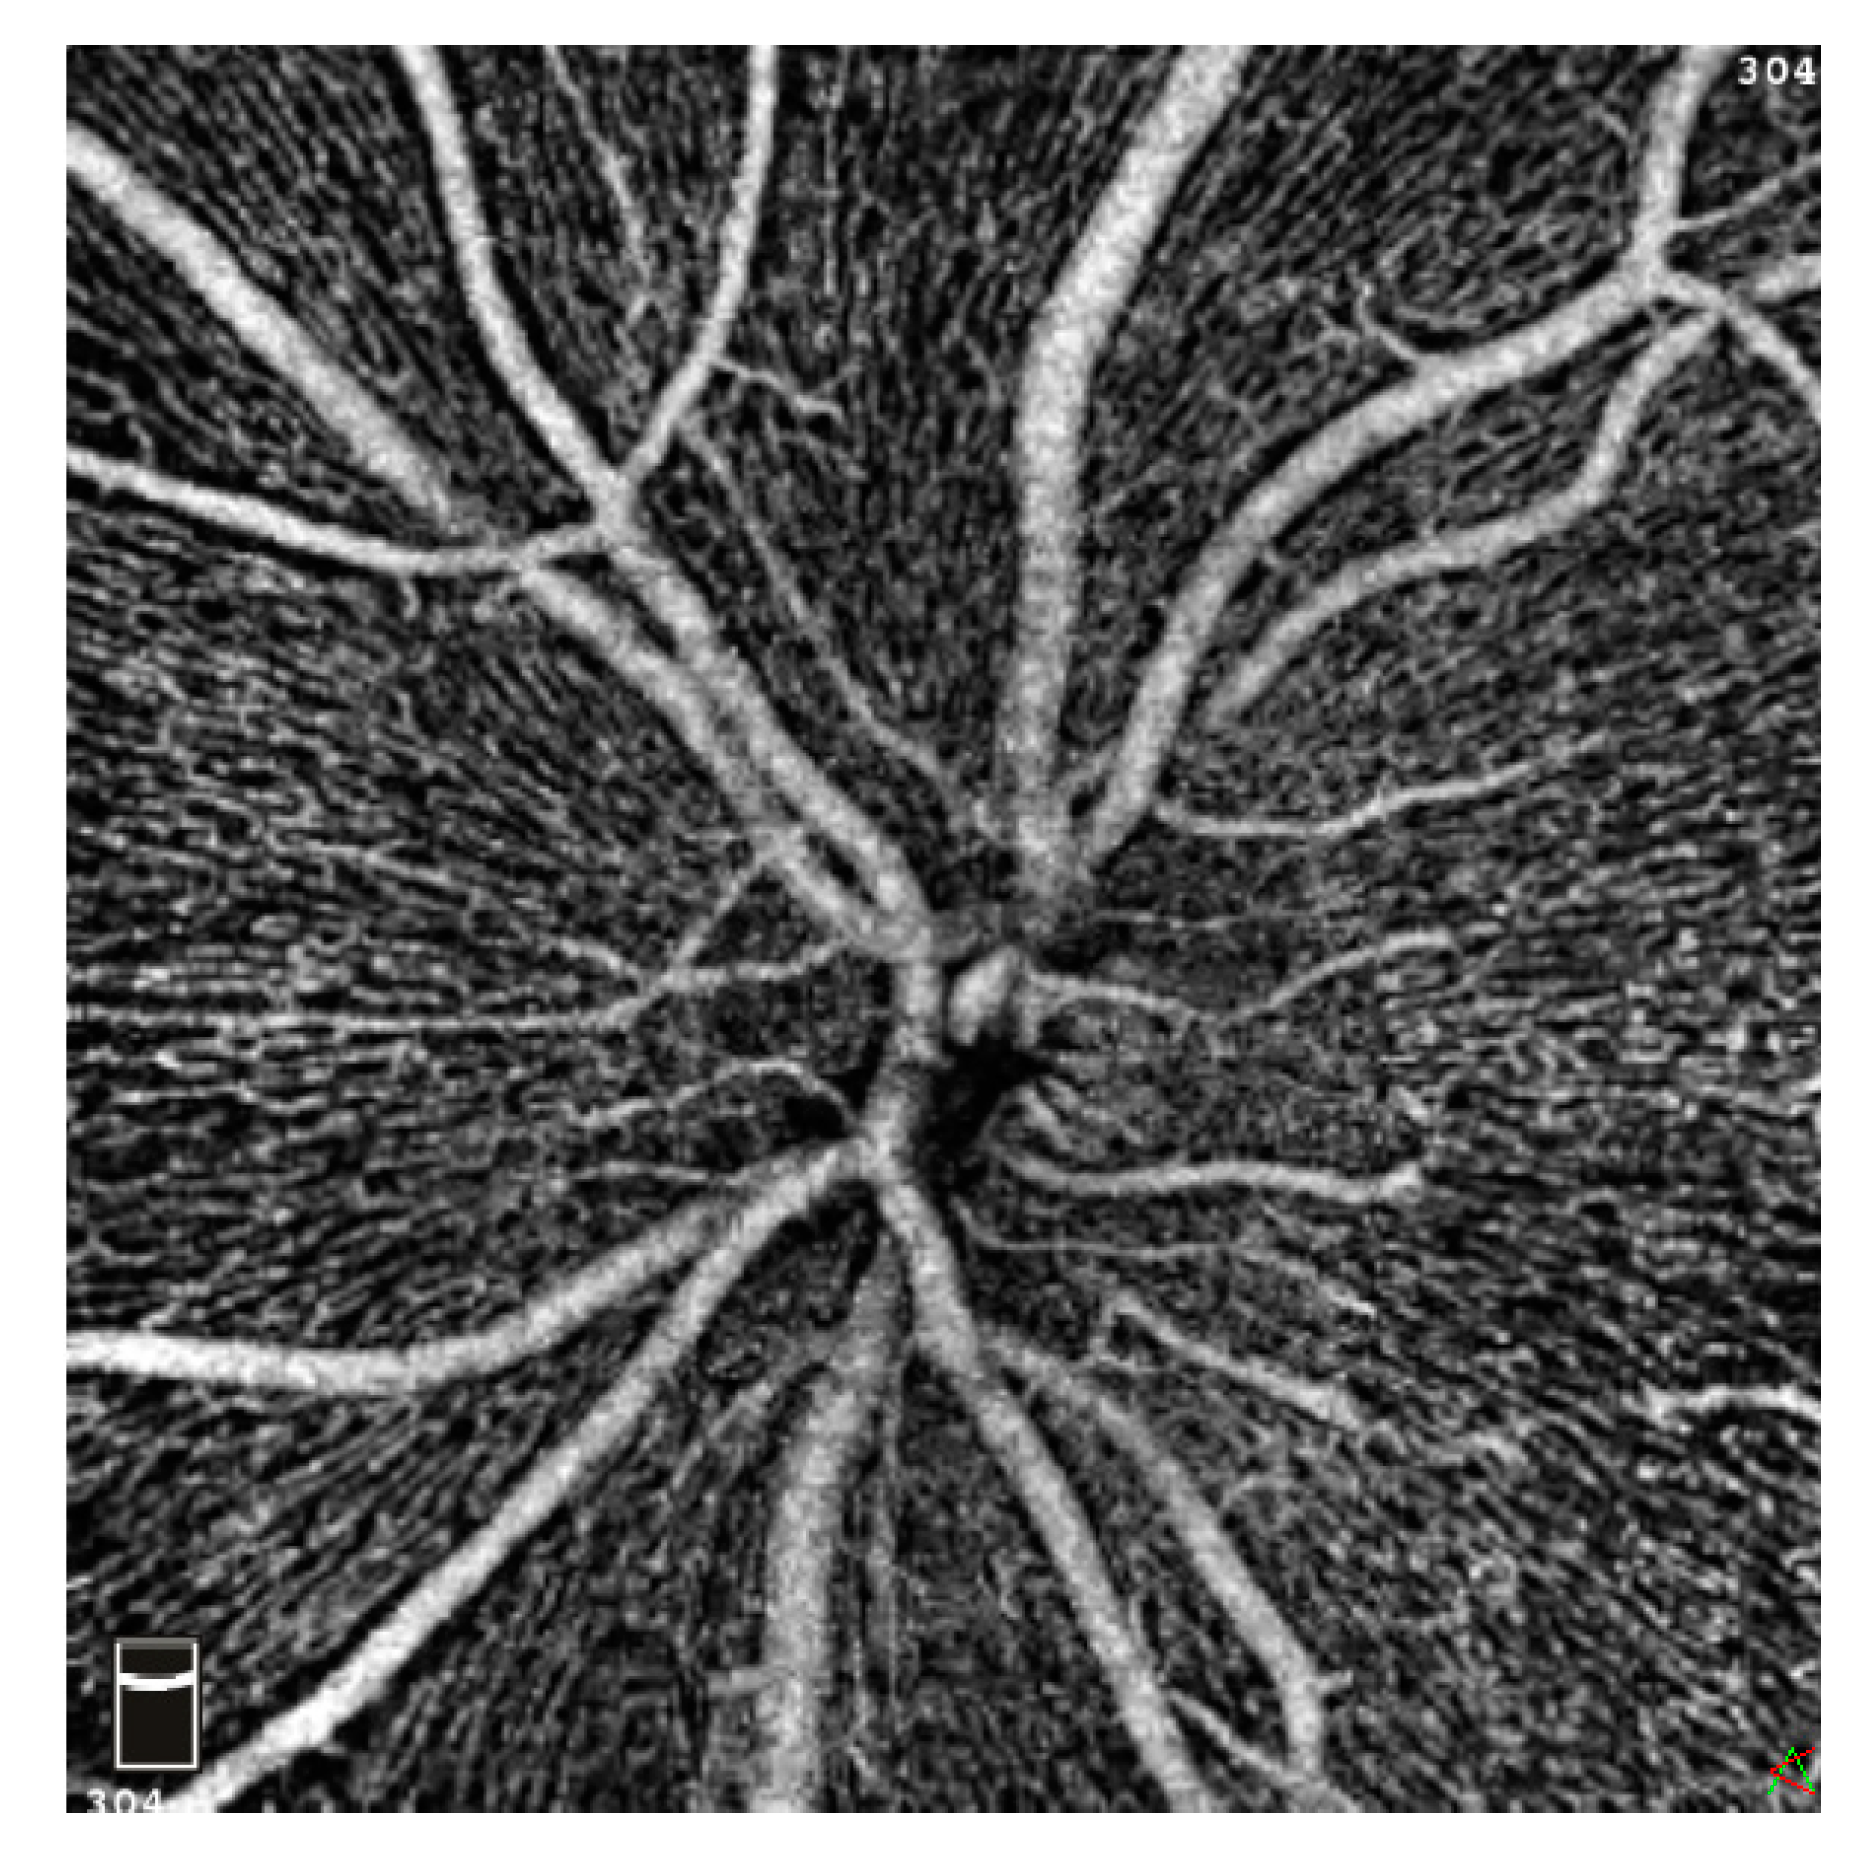

2. Materials and Methods

2.2. Patient Examination